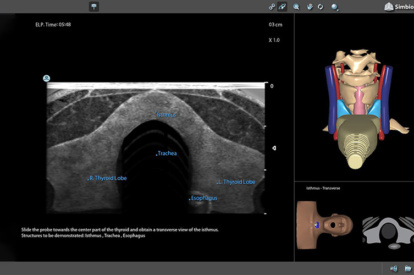

Ultrasound Mentor accelerates the development of basic to advanced technical and cognitive skills, by providing not only the probe manipulation training, but also a didactic environment enabling structured, self-guided learning including step-by-step instructions and educational aids such as 3D anatomical map and probe positioning assistant, all backed up with our progress monitoring tool MentorLearn.

Neck Module